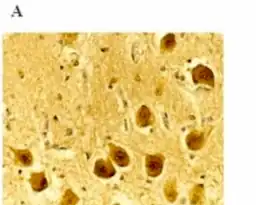

Diagnosis

.png.webp)